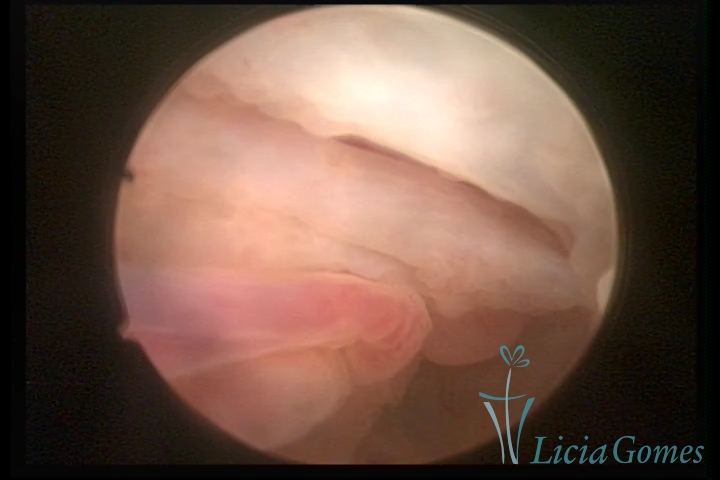

Second part or middle section

In the middle section of the cervical canal, the details of the buds are lost. It is possible to view creases and crypts. Longitudinal grooves are frequently observed. They are the most compact tissues presenting the most vascularized surface, whose vessels follow its passageway.